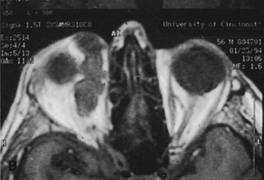

small lateral canthotomy incision measuring 1 to 1.5 cm in length (Figs. 10, 11, and 12). With wide undermining in the suborbicularis plane and retraction

always can be extended farther posteriorly if exposure is inadequate.   Figure 10. A. Large, well-encapsulated intraconal mass on MR scan. B. Small lateral canthotomy incision will be used to perform lateral orbitotomy

and remove the intraconal mass.

Figure 10. A. Large, well-encapsulated intraconal mass on MR scan. B. Small lateral canthotomy incision will be used to perform lateral orbitotomy

and remove the intraconal mass.